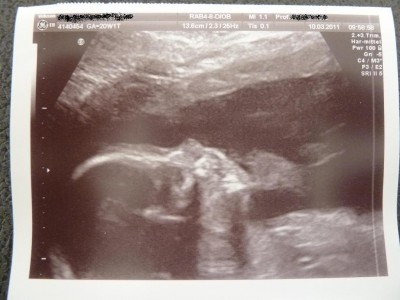

Ansonsten war der kleine Mann wie immer Fotoscheu. Er hat IMMER die Händchen vor dem Gesicht gehabt. Insofern hatten wir nicht viel vom kurzen Umschalten auf 3D. Aber süße Patschehändchen hat er, das wissen wir jetzt genau.

Anbei noch 2 Bildchen. Auf dem einen ist das Profil, nicht sehr gelungen aufgrund der Schwierigkeiten, die der Kleine beim Fotografieren macht. Auf dem anderen ist ein Füßchen zu sehen. Das Füßchen ist immerhin schon 3,5 cm lang –Wahnsinn, oder??????????